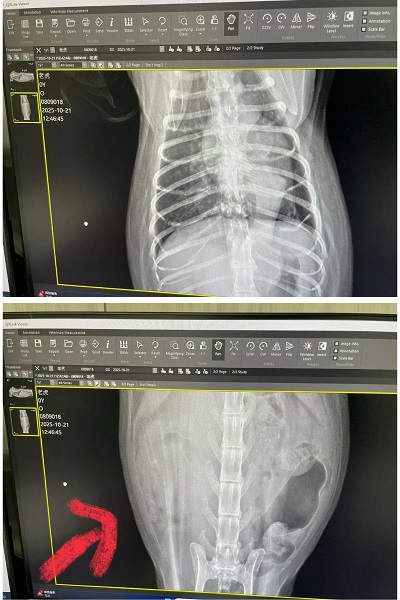

2025年6月2日回診的皮膚改善不夠理想、要更換黴菌藥,也還有些小顆粒要繼續刷洗,比較讓人擔心的是除了肝指數升高,紅血球及血容比持續下降,懷疑體內有其他地方在出血,因此在2025年6月16日回診的紅血球仍在下降及白血球也開始下降時,做超音波及X光檢查進一步查看,結果發現心臟尺寸較大,再加驗心臟快篩結果異常,且脾臟也有腫大、右腎上方有一個跟腎臟本身一樣大的腫瘤。

2025年10月因老虎瞳孔放大精神狀況不佳而於同月21日回診,目前體重下降有些快但目前食慾精神還算穩定,還沒有出現症狀,右腎腫瘤過大問題採安寧照護,暫時也不需要回診,有食慾不好的狀況,可再回診拿類固醇跟止痛等藥物舒緩。若狀況持續變差則可向醫院領取嗎啡貼片及止痛藥。

至目前老虎的精神食慾尚可,但已來到末期的安寧照護,只希望盡可能讓老虎在最後階段能減緩身體的不適。本筆醫助是2025年6月26日於專心醫院及2025年6月30日至2025年10月21日間於沐恩醫院的費用,包含血檢、超音波、X光及用藥。

2025/10/21 老虎 沐恩 林院長

體重:4.435kg (6/30是5.61kg)

一、看診情形

請醫師協助剪指甲。體重掉稍微比較多,腫瘤引起比較有關係

皮膚跟體力有影響關係,右腎腫瘤過大只做安寧照護就先維持

胸有點不明物體不確定是什麼物體(也有可能是瘦太快皮膚皺摺陰影),有明顯的呼吸聲,也不像肺部轉移物質,超音波檢查是沒事。

皮膚部分只能梳毛或清水擦拭。肝腎功能指數都還正常。